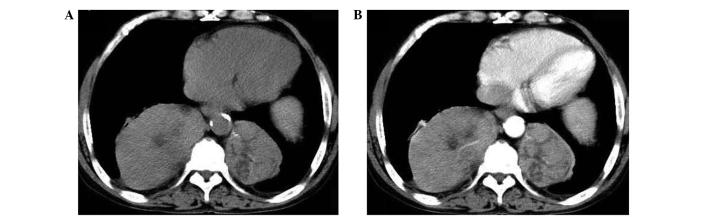

Extramedullary hematopoiesis (EMH) is a rare disease that is characterized by the presence of hemopoietic tissue outside the bone marrow. The masses that form are usually microscopic and asymptomatic, but occasionally lead to tumor-like masses. A 56-year-old male who initially presented to the First Affiliated Hospital, School of Medicine, Zhejiang University (Hangzhou, China) with upper abdominal pain and jaundice was found to have paravertebral masses in the thorax. Histopathological examination of a computed tomography-guided needle aspiration biopsy of the masses revealed EMH. The current study presents this unusual case, in which EMH was diagnosed by chance in a patient with hereditary spherocytosis. As the intrathoracic EMH was asymptomatic, the patient was discharged with the proviso of regular follow-up examinations. The patient exhibited improved blood cell counts following a splenectomy to reduce the hemolysis and stabilize the thoracic masses. The thoracic masses have been closely followed for one and a half years. A correct diagnosis can thus aid in avoiding unnecessary surgical intervention, particularly in an asymptomatic patient.

髓外造血(EMH)是一种罕见疾病,其特征是骨髓外存在造血组织。形成的肿块通常是微观的且无症状,但偶尔会导致肿瘤样肿块。一名56岁男性最初因上腹部疼痛和黄疸就诊于浙江大学医学院附属第一医院(中国杭州),发现胸部有椎旁肿块。对肿块进行计算机断层扫描引导下针吸活检的组织病理学检查显示为EMH。本研究报告了这一罕见病例,其中一名遗传性球形红细胞增多症患者偶然被诊断为EMH。由于胸内EMH无症状,患者在定期随访检查的条件下出院。患者在进行脾切除术后血细胞计数有所改善,以减少溶血并稳定胸部肿块。对胸部肿块进行了一年半的密切随访。因此,正确的诊断有助于避免不必要的手术干预,尤其是对于无症状患者。